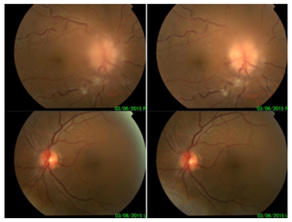

A 52-year-old man with a history of multiple myeloma recently started on bendamustine/bortezomib/dexamethasone therapy one month prior to presentation had noted temporary vision loss in his right eye two weeks prior to presentation. The episode lasted 10minutes and resolved spontaneously. Two weeks later, he again experienced sudden, painless vision loss in the right eye with mild photophobia, which did not resolve. When he presented two days later, he denied any ocular trauma, headache, neck stiffness, nausea, vomiting or focal neurologic symptoms. He had been diagnosed with IgG kappa multiple myeloma five years prior with partial remission after cyclophosphamide/bortezomib/dexamethasone therapy, followed by Velcade, Thalidomide, and Cytoxan. He underwent stem cell transplantation one year after the initial diagnosis and had experienced multiple relapses. Ophthalmologic examination at presentation revealed no light perception (NLP) in the right eye and best corrected visual acuity was 20/25 in the left eye, with a relative afferent pupillary defect in the right eye. There was florid edema of the right optic disc with flame-shaped hemorrhages. We also found multiple cotton-wool spots, Roth’s spots, and tortuous retinal vessels (Figure 1). His vital signs were stable, with a blood pressure of 101/59. There were no other focal neurologic deficits.

Figure 1 Fundus photographs. OD: Florid disc edema with CWS and tortuous vessels.